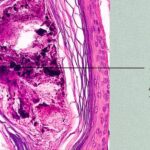

Traction Alopecia Traction alopecia is another type of mechanical alopecia, usually resulting from a variety of hair-styling practices, particularly in African-Americans, that includes tight braids, corn rows, straightening, and the use of sponge rollers . Hair follicle injury is similar to that produced in trichotillomania, but in traction alopecia there are differences that relate to the use of less force over a greater period of time (194). Traction alopecia is often classified clinically and histologically as "early" and "late" disease . In early disease, tension on hair follicles exists over the course of months to a few years, sometimes presenting as a traction folliculitis with perifollicular erythema and pustules . In late disease, hair is subject to traction over many years. In early disease, discontinuation of the abnormal forces on the hair leads to regrowth of hair, but in late disease, follicles are lost, producing a permanent alopecia. Early and late disease are commonly found together in the same patient; as permanently scarred areas develop (late disease), terminal hairs at the periphery are used in styling, becoming the new target of traction (early disease) (. Occupationally related traction alopecia has been reported due to wearing of a nurse's cap, occurring at the site of pin placement used to secure the cap . Histopathology. In early traction alopecia, the histologic findings are similar to those of trichotillomania, albeit more subtle (194). For instance, the density of follicles is normal, with a normal number of vellus hairs. Premature conversion of anagen hairs to catagen occurs, resulting in an increased number of catagen and telogen follicles. Pigment casts and trichomalacia are sometimes found, although less often than in trichotillomania. Inflammation is absent. |

outnumbering terminal follicles. In late |

disease, the pathology shows an "end-stage" scarring alopecia, a histologic picture shared by many forms of permanent alopecia at an advanced stage. Pigment casts and trichomalacia are not seen in late traction alopecia. |